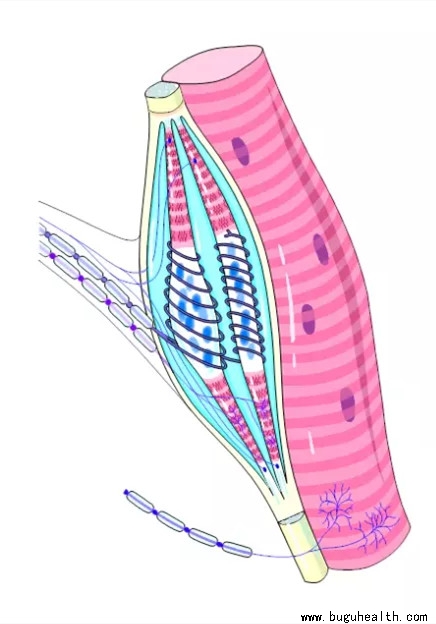

- 布骨医学科普:肌肉能量技术的治疗流程 布骨康复医疗中心 ,2021-09-13

- 患者的肢体被移动至能感受到阻力的位置,即束缚点。在治疗的目标区域中对一个稍微仅次于束缚点的点进行放松治疗,对于患者来说会更容易接受,尤其是当这些组织处于病症慢性阶段时。嘱患者使用10%~20%的肌肉力量来抵抗由治疗师施加的阻力,使待治疗的肌肉或拮抗肌进行等长收缩。若采用等长收缩后放松(PIR)的方法.....